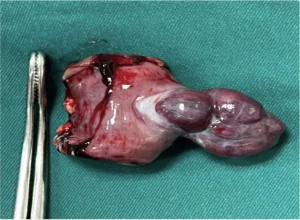

Se realiza laparotomía exploratoria (imagen 4) más exéresis de hemangioma, más resección de yeyuno 15 cm, más anastomosis primaria, encontrando adherencias de epiplon mayor a útero y anexos, firmes, hemangioma pediculado a nivel de yeyuno, a 30 cm del ángulo de treitz, mide 3 cm de diámetro (imagen 5) dependiente de borde antimesentérico. Se toma muestra para estudio histopatológico e inmunohistoquímico.

Imagen 4. Exploración quirúrgica

Imagen 5. Hemangioma pediculado